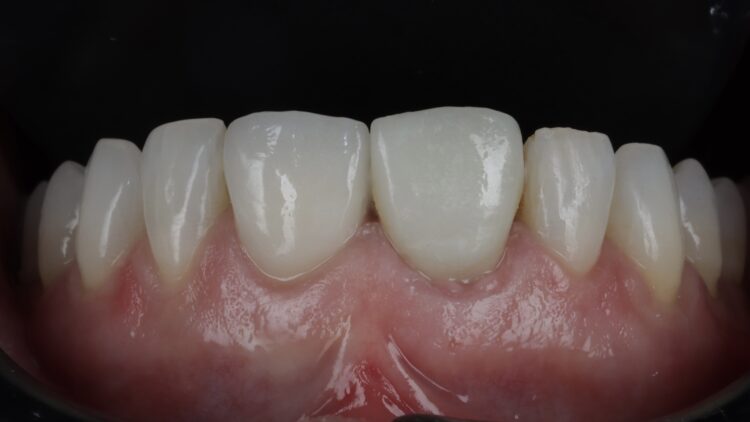

Upon review eight weeks later, healing had been uneventful. The temporary restoration will be left in place for six months to allow the tissues to mature prior to final restoration.

The CONELOG® implant system is my go-to for immediate cases, particularly where strength and function must be balanced with aesthetics. Its long conus reduces micromovements and it affords greater positional stability than other conical systems I have used. The 3.8mm diameter is the ideal combination of surgical strength and aesthetic considerations. The Guided Surgical Kit is simple to use and has a streamlined workflow for increased efficiency.